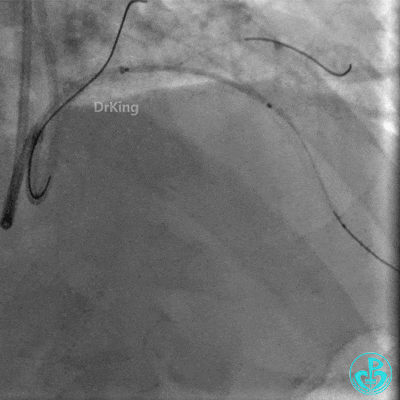

逆向Sion、M6导丝无法到达前降支近端真腔。

明胶在血管怎么降解并发症丨前降支CTO同侧逆向开通时侧支血管破裂,弹簧圈联合明胶海绵封堵_https://www.jmylbn.com_新闻资讯_第23张

明胶在血管怎么降解并发症丨前降支CTO同侧逆向开通时侧支血管破裂,弹簧圈联合明胶海绵封堵_https://www.jmylbn.com_新闻资讯_第24张